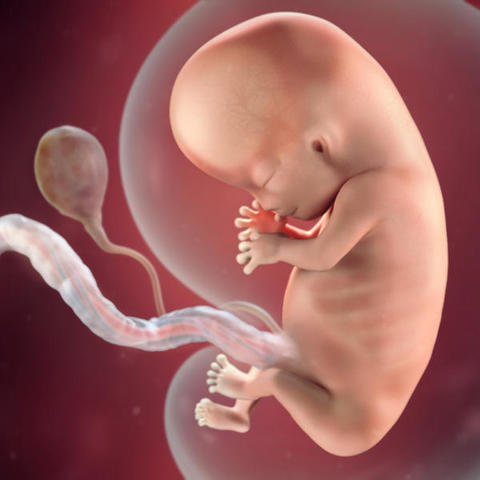

• Semana 9 - Inicia el periodo fetal

Semana 9 - Inicia el periodo fetal

Mide entre 17 y 22 milímetros. Y físicamente también ha cambiado mucho: la cola ha desaparecido y la cabeza se ha separado un poco del cuerpo gracias a un incipiente cuello que humaniza su silueta.

- Los ojos se acercan entre sí, mientras que los párpados empiezan a formarse y casi cubren los ojos. Ya ha aparecido el labio.

- Se forman los pezones y los folículos pilosos.

- Los brazos crecen y se desarrollan los codos.

- Se pueden observar los dedos del pie del bebé.